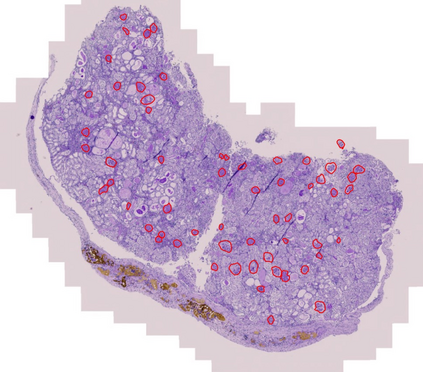

In digital pathology, the traditional method for deep learning-based image segmentation typically involves a two-stage process: initially segmenting high-resolution whole slide images (WSI) into smaller patches (e.g., 256x256, 512x512, 1024x1024) and subsequently reconstructing them to their original scale. This method often struggles to capture the complex details and vast scope of WSIs. In this paper, we propose the holistic histopathology (HoloHisto) segmentation method to achieve end-to-end segmentation on gigapixel WSIs, whose maximum resolution is above 80,000$\times$70,000 pixels. HoloHisto fundamentally shifts the paradigm of WSI segmentation to an end-to-end learning fashion with 1) a large (4K) resolution base patch for elevated visual information inclusion and efficient processing, and 2) a novel sequential tokenization mechanism to properly model the contextual relationships and efficiently model the rich information from the 4K input. To our best knowledge, HoloHisto presents the first holistic approach for gigapixel resolution WSI segmentation, supporting direct I/O of complete WSI and their corresponding gigapixel masks. Under the HoloHisto platform, we unveil a random 4K sampler that transcends ultra-high resolution, delivering 31 and 10 times more pixels than standard 2D and 3D patches, respectively, for advancing computational capabilities. To facilitate efficient 4K resolution dense prediction, we leverage sequential tokenization, utilizing a pre-trained image tokenizer to group image features into a discrete token grid. To assess the performance, our team curated a new kidney pathology image segmentation (KPIs) dataset with WSI-level glomeruli segmentation from whole mouse kidneys. From the results, HoloHisto-4K delivers remarkable performance gains over previous state-of-the-art models.